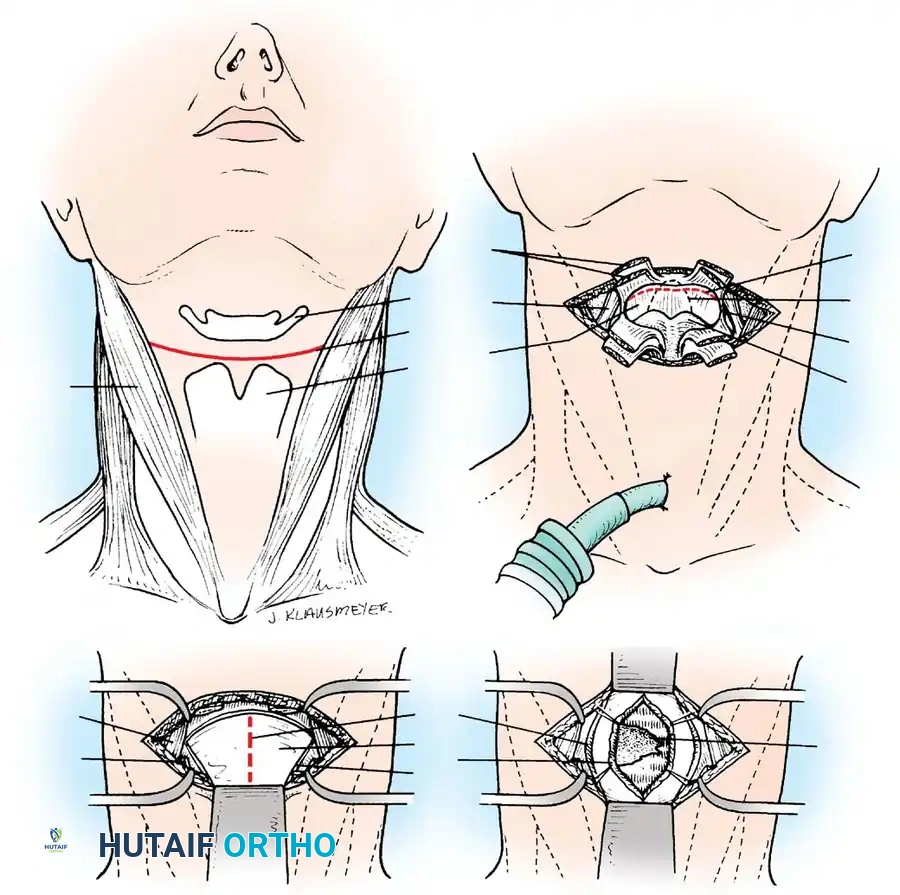

The Transthyrohyoid Approach:

* Make a transverse collar incision along the uppermost crease of the neck, between the hyoid bone and the thyroid cartilage, extending laterally to the carotid sheaths.

* Divide the sternohyoid and thyrohyoid muscles to expose the underlying thyrohyoid membrane.

* Detach the thyrohyoid membrane as close to the hyoid bone as possible. This superior detachment is critical to avoid iatrogenic injury to the internal laryngeal nerve and superior laryngeal vessels, which pierce the membrane near its inferior attachment.

* Enter the hypopharynx by incising the exposed mucous membrane from the lateral aspect to avoid damaging the epiglottis.

* Retract the hyoid bone superiorly and the epiglottis anteriorly. Make a midline incision through the posterior pharyngeal wall down to the bone.

* Raise subperiosteal flaps bilaterally to expose the bodies of C2, C3, and C4.